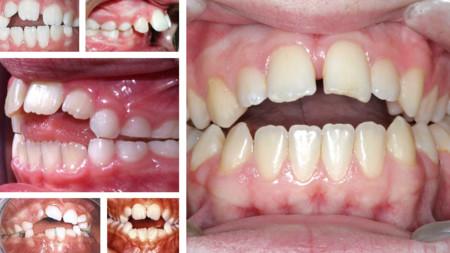

Maloclusión dentaria: al estar el dedo interpuesto entre los dientes de arriba y de abajo, no hay contacto entre ellos. Los dientes superiores se van desplazando hacia delante dejando un hueco creado por el dedo, cuando el dedo no está en la boca se ve claramente que hay una mordida abierta, los dientes anteriores no tienen contacto.

mordiada abierta por succión del dedo pulgar

Mordida abierta.

Mordida abierta: el uso del chupete en niños mayores de 4 años puede ocasionar una mordida abierta, al cerrar los dientes se queda un  hueco entre los dientes superiores e inferiores. La mordida abierta provocada por el chupete suele ser menos pronunciada que con la succión del dedo pulgar. (Dejo vídeo al final para que lo entendáis mejor)